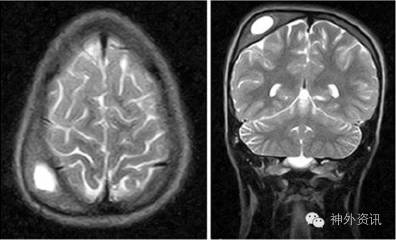

11岁女性患者,出生时借助产钳分娩导致双侧顶部头颅血肿。产后1月左右左侧血肿基本吸收,右侧血肿逐渐钙化,当时医生没有建议手术。女孩成长过程中没有出现与血肿相关的躯体或神经精神方面的问题。然而,神经心理测试发现有学习上的障碍,包括轻度的注意力不集中。为此,进行脑电图检查(EEG),当时没有显示异常。10岁左右的随访EEG中出现不对称α波活动背景下的右侧额顶部低振幅、散在的棘波(图1)。头颅MRI检查提示,右顶部头颅血肿,厚度25mm,伴有颅骨内层改变和脑实质中度受压(图2)。3月后复查EEG的结果同前。患儿有轻度头痛,并要求美容手术。

图2. 术前MRI-T2像显示右额顶部头颅血肿。